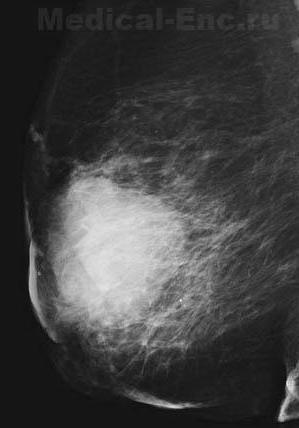

![]() Рак молочної залози (цифрова мамограма) |

Рак молочної залози серед злоякісних пухлин у жінок посідає одне з перших місць. У чоловіків спостерігається рідко. У початковій стадії рак молочної залози являє собою невеликий одиночний, щільний, негладкий, безболісний вузол, який, поступово збільшуючись, проникає в шкіру, фасції, м'язи. Метастази зазвичай раніше з'являються в регіонарних лімфатичних вузлах (подкрыльцовых, під - і надключичних, загрудинний), потім у віддалених органах, найчастіше в легенях, печінці, кістках.

Протягом раку молочної залози прийнято умовно поділяти на чотири стадії. Стадія I - пухлина діаметром менше 3 см розташовується в залозі, метастазів немає. Стадія ІІа - пухлина до 5 см, переходить на клітковину. При спробі зібрати в складку шкіри над пухлиною з'являється зморшкуватість шкіри - симптом втягнення (рис. 2); регіонарних метастазів немає. Стадія ІІб - те ж, що стадія ІІа, але є метастази в подкрыльцовые лімфатичні вузли. Стадія III (а і б) - пухлина різної величини з множинними метастазами в подкрыльцовые, підключичні або підлопаткові лімфатичні вузли. Про ураженні регіонарних лімфатичних вузлів метастазами з порушенням відтоку лімфи свідчить поява симптому «апельсинової кірки» на шкірі над пухлиною (рис.3). У цій же стадії спостерігається воронкоподібне втягнення шкіри над пухлиною. Стадія IV - рак молочної залози з розповсюдженням у віддалені органи.